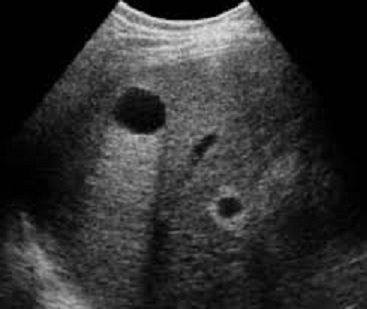

- Image echographique

de kyste simple du foie est :

Aspect lesionel anechogene , homogene ,arrondie ou ovalaire a

renforcement echoriche posterieur . Sa contour est. net , lisse

, peut etre en cloisone et avascularisation

Aspect lesionnel du kyste est arrondie aechogene a

bord tres nette et lisse , situe

a lobe droit du foie . Ombre de hyperascoustique porterieure

du kyste en visualise tres net . Image echographie

percutanee du kyste simple du foie |

Kyste multiple simple du foie

droit . Le kyste inferieure est en vue tres nette

avec encloisonne